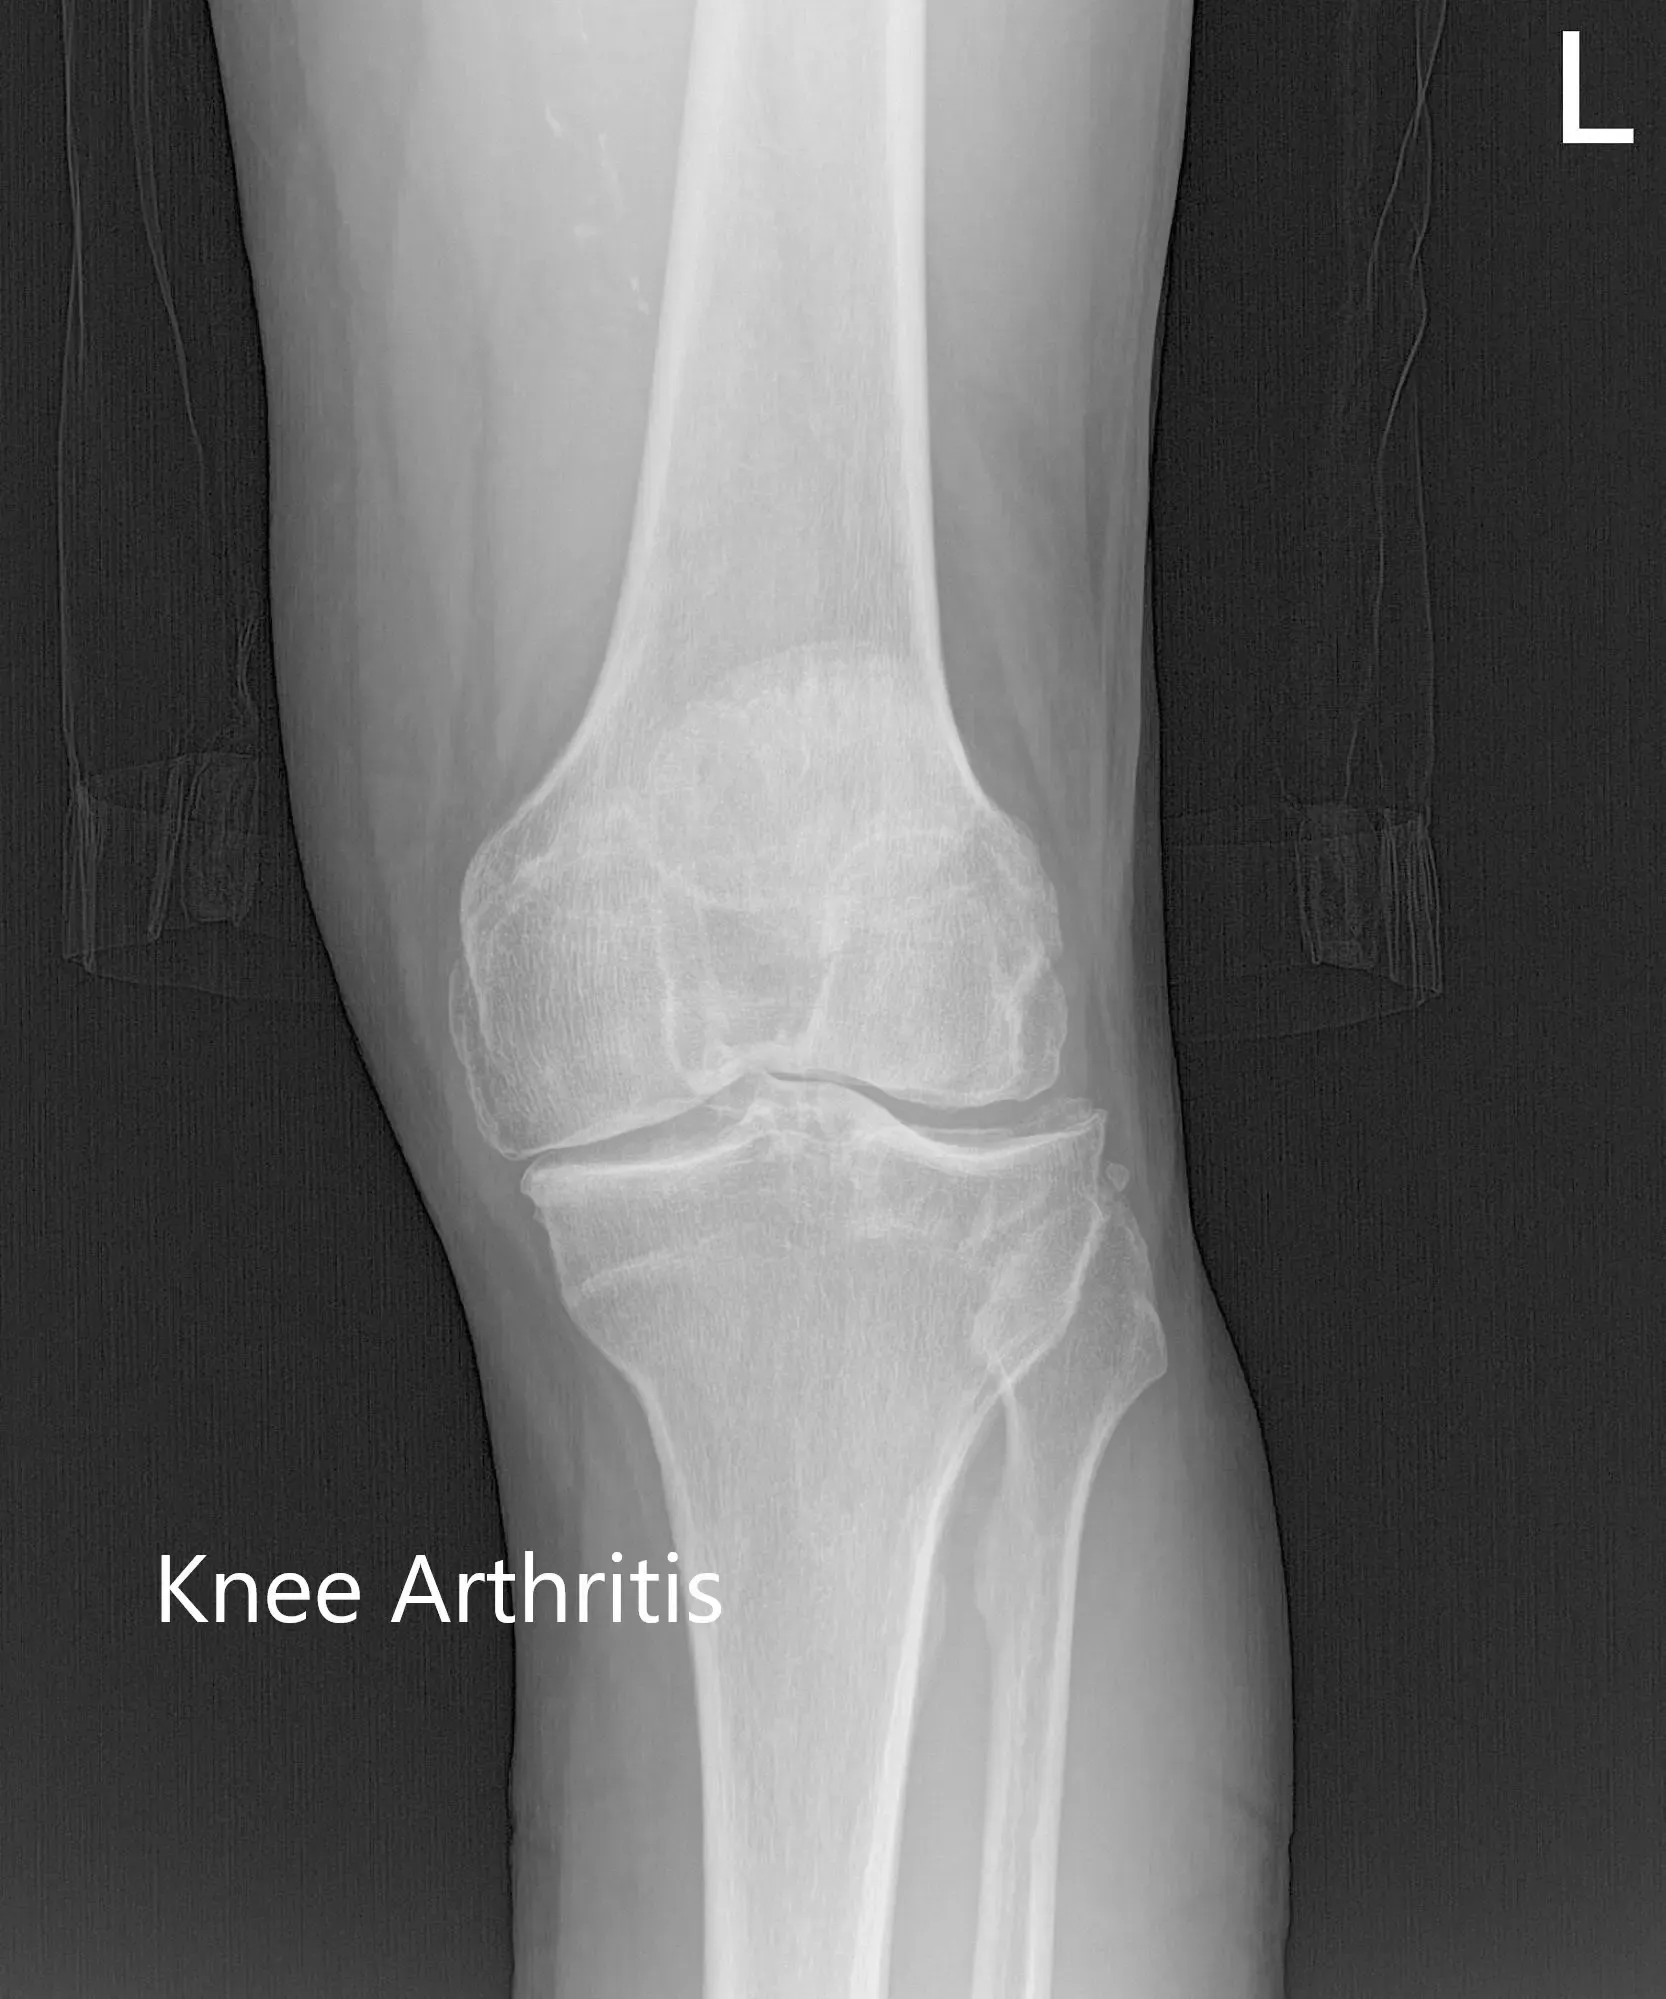

There was no distal neurological deficit and the bilateral pulses were good volume and comparable. Imaging studies revealed severe tricompartmental osteoarthritis of the left knee. Considering the patient’s lifestyle limiting knee pain, she was advised customized left knee total replacement. Risks, benefits, and alternatives were discussed with her at length. She agreed with the plan.

Preoperative X-ray of the left knee showing AP, lateral and merchant views